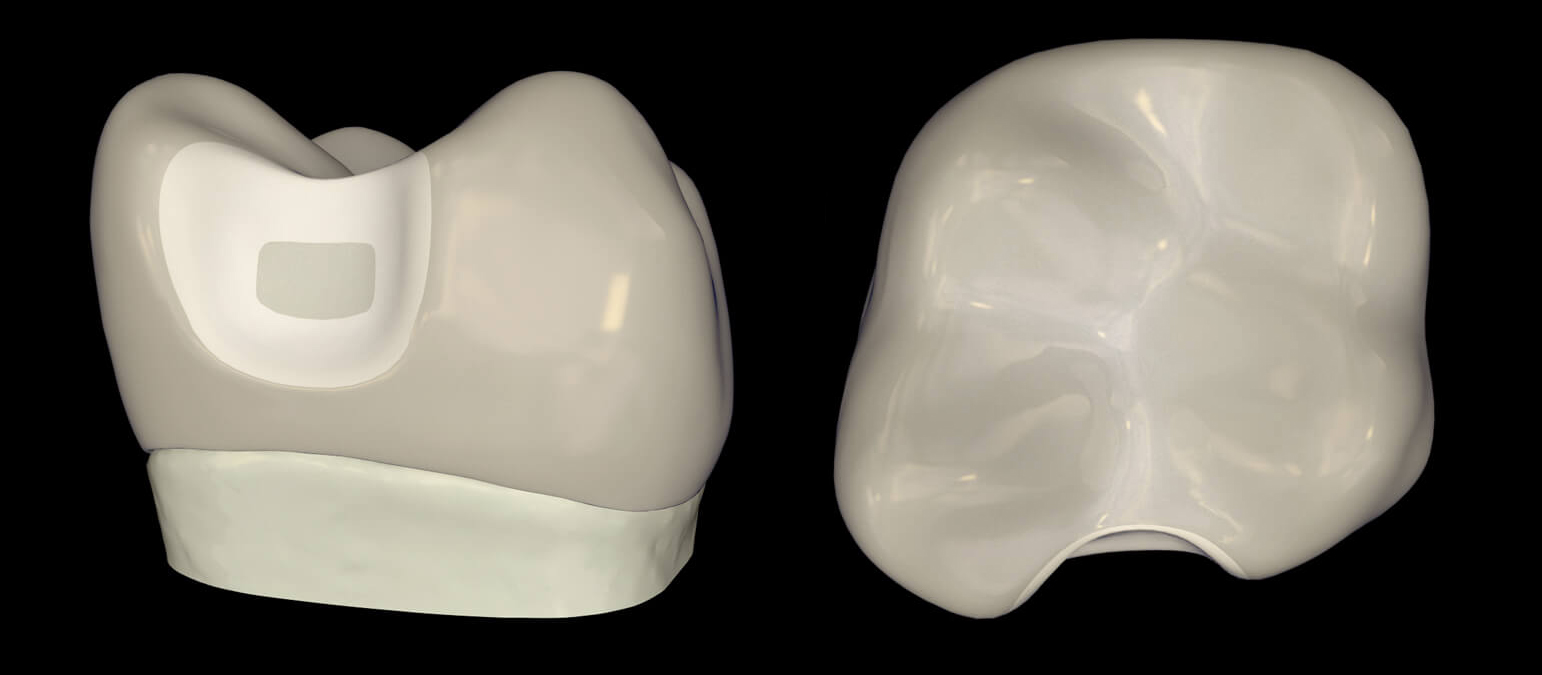

Learn about the more conservative modern class II preparation that is uniquely suited to the Bioclear Method.

Learn about the more conservative modern class II preparation that is uniquely suited to the Bioclear Method.

Follow along with Dr. Clark as he goes through the 5 steps to successfully complete a modern composite restoration using Bioclear’s new Biofit Posterior System.

Injection Molding a Modern Class II – An Introduction to Bioclear’s Biofit HD Matrix, Diamond Wedge, and Twin Ring